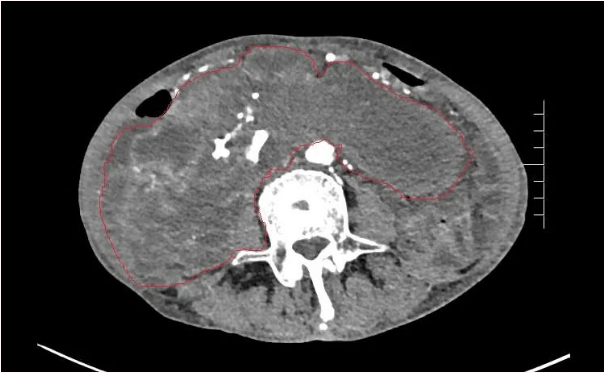

患者王大爺,男,72歲,發(fā)現(xiàn)腹腔腫物10余年,近兩年來患者雙下肢乏力、貧血,依靠間斷輸血維持著正常生活,出現(xiàn)頭昏,行動困難,腹部疼痛及便血慕名來我院就診。入院后查體評估患者年齡大,體質(zhì)差,嚴重貧血,肺部感染及腸梗阻征象,腹部增強CT檢查提示腹膜后巨大腫瘤,長徑超過30厘米,占據(jù)大部分腹腔,并可能存在雙原發(fā)腫瘤。

苗滿園腫瘤外科團隊在麻醉科/手術室的緊密配合下為該患者進行手術,術中發(fā)現(xiàn)腫瘤巨大,幾乎占據(jù)了整個腹腔,從左側(cè)向右腹腔延伸,向上將肝、腎擠向膈下,向左將胃及小腸擠向左上腹,向下深達盆腔內(nèi),包繞下腔靜脈、腸系膜上動脈等大血管及輸尿管,回盲部及回腸也受侵犯。手術難度巨大,風險極高。團隊憑借著高超的手術技能和精準的手術預案沉著應對,迎難而上,應用高頻電刀、超聲刀、切割縫合器等先進設備,耗時近5小時為患者切除了巨大腹腔腫瘤,并聯(lián)合右半結(jié)腸切除,術中出血僅50ml。術后病理為腹膜后巨大平滑肌瘤+回腸腺癌。